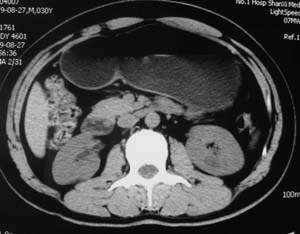

以下是引用子期在2010-3-19 20:47:00的发言:[br]血管畸形的ct增强应该有明显强化,本例并不相符合。本例双肾局部的略低密度影,累及肾盂,局部皮质明显变薄、内陷,增强扫描有轻度的强化,应考虑为炎性病变,患者为年轻男性,累及双肾的感染以结核较常见,可以没有明显的临床症状,尿中有时候也并不能查出什么;肾脓肿常有明显感染中毒症状,本例不符,另外一般的肾盂肾炎或肾小球肾炎通过小便就可确诊,其它还不能排除的是黄色肉芽肿性肾盂肾炎,然而单凭ct一般也很难鉴别。